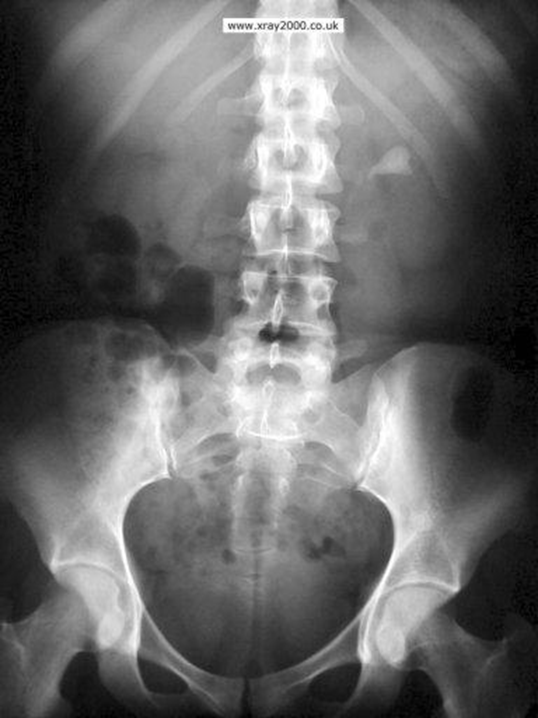

БОЛИТЬ НИЖНЯ КІНЦІВКА. ЧЕРЕЗ ЯКІ ОТВОРИ І ЯКОГО ВІДДІЛУ ХРЕБТА МОЖУТЬ ВИХОДИТИ НЕРВИ?

ЛЮМБАЛЬНОГО ВІДДІЛУ ХРЕБТА

ПОПЕРЕКОВОГО ВІДДІЛУ ХРЕБТА

КРИЖОВОГО ВІДДІЛУ ХРЕБТА

САКРАЛЬНОГО ВІДДІЛУ ХРЕБТА

ЯКІ ВИГИНИ ХРЕБТА ВИ БАЧИТЕ НА РЕНТГЕНОГРАМІ?

НА ЯКІЙ РЕНТГЕНОГРАМІ Є КІСТКИ, ЩО НЕ НАЛЕЖАТЬ ДО СКЕЛЕТУ НИЖНЬОЇ КІНЦІВКИ?